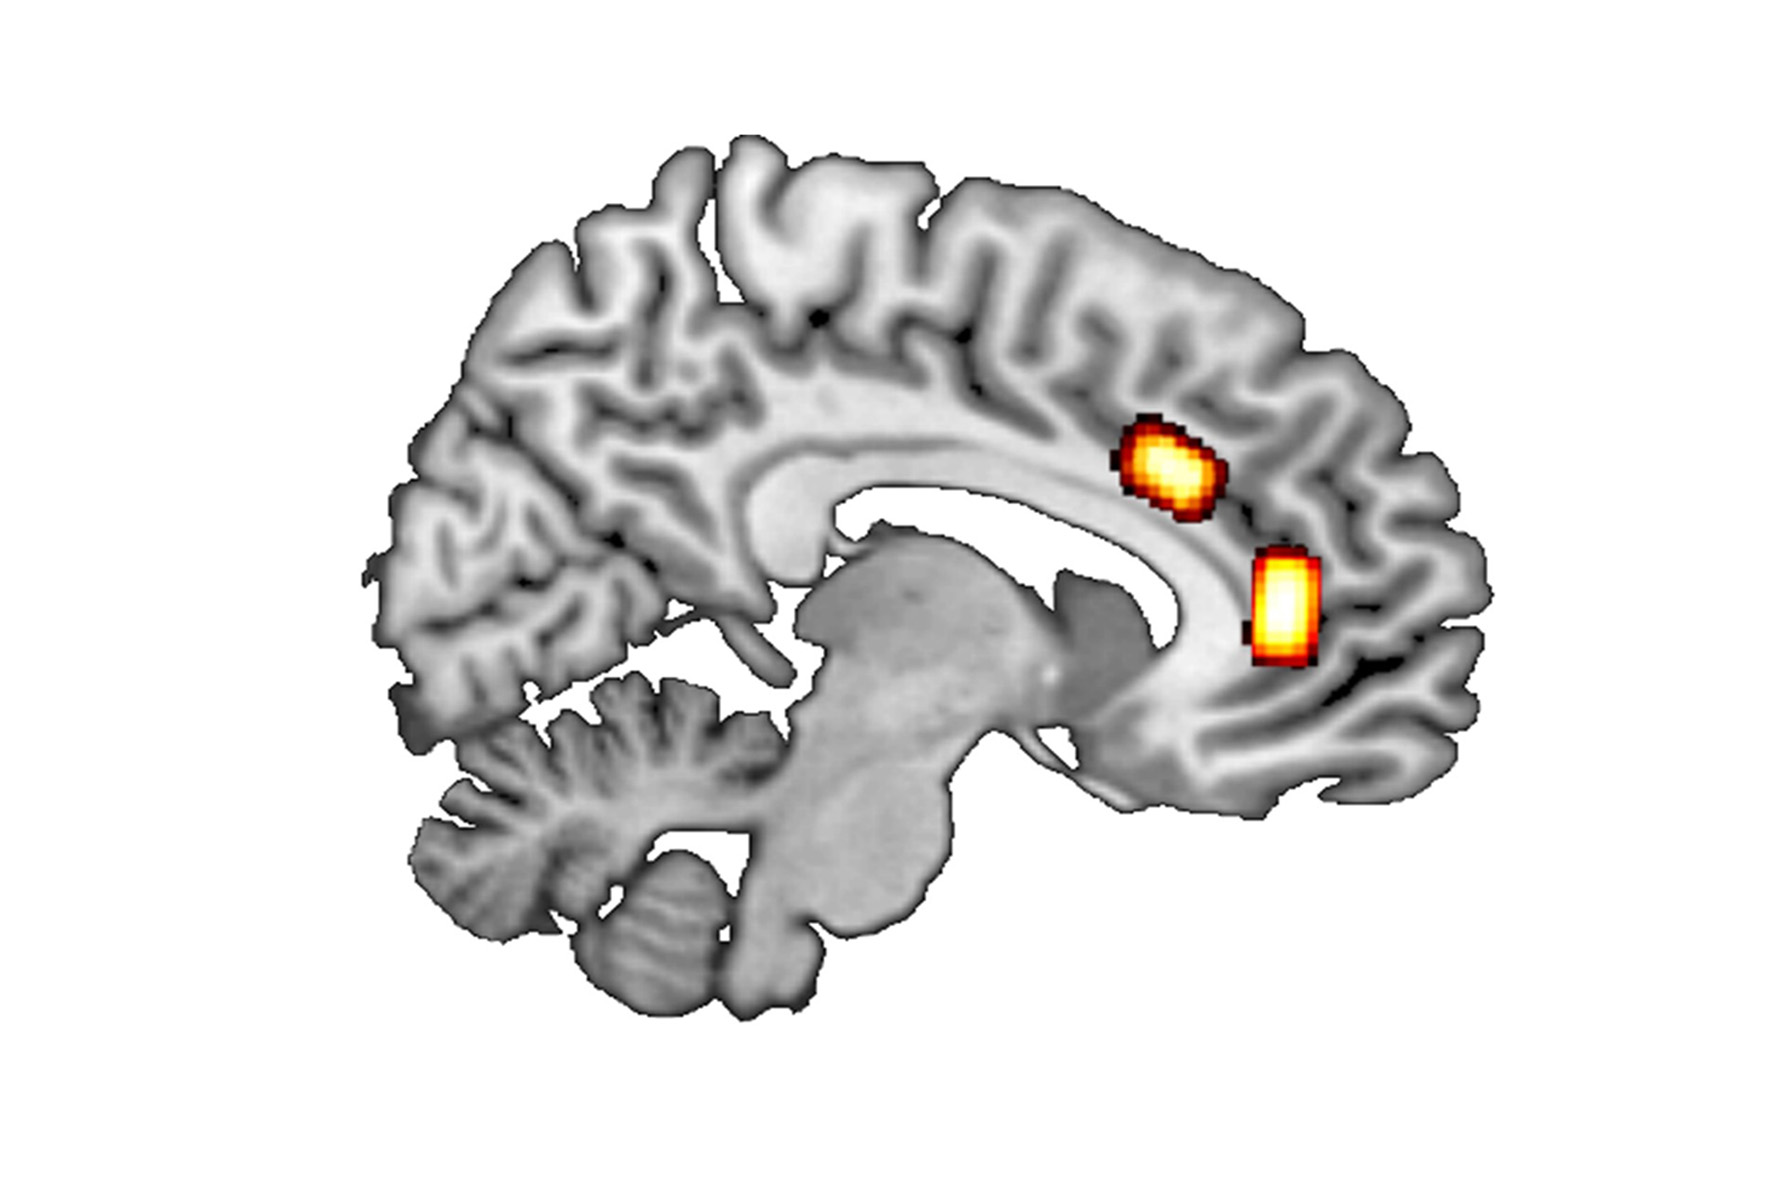

On the one hand, the researchers looked at ‘reward-based decisions’, which involve maximising reward by selecting the better of two current options. Luca Kaiser gives a simple example: “Where do I buy coffee on my way to work, depending on the price, quality and whether or not the café is on my way?” Previous results suggest that such decision-making processes in the brain are mainly processed in the ventromedial prefrontal cortex (vmPFC).

‘Patch-leaving decisions’ are about long-term strategic issues that include an extensive balancing of cost against gain. An example of such a decision would be whether to move from Düsseldorf to Munich for a job offer. Prof. Jocham explains: “The job in Munich may offer a higher salary and a more interesting role, but may also involve stress and the effort involved in finding a place to live and moving to Munich as well as higher rents and the loss of social contacts in Düsseldorf.” So there are many factors that influence this type of decision. According to the literature, such decisions are made in the brain’s dorsal anterior cingulate cortex, or dACC for short.

The team then used the data to correlate the ratio of the two messenger substances with the individual decision-making behaviour of the subjects. In the patch-leaving scenario, subjects with a higher ratio of GABA to glutamate in dACC were quicker to leave a depleting resource. By contrast, people with higher concentrations of glutamate needed a greater quality improvement before deciding to leave their current patch.

In the other scenario, subjects with higher concentrations of GABA relative to glutamate in vmPFC exhibited significantly increased decision accuracy. They were more reliable at selecting the higher-value option.